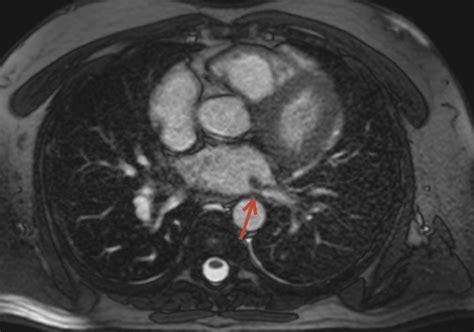

Magnetic Resonance Imaging (MRI) Offers high-resolution images of the pulmonary veins and heart, useful for assessing blood flow and detecting stenosis.